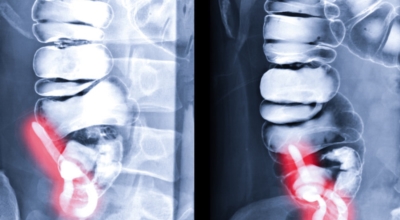

맹장염은 맹장 끝 충수돌기에 발생하는 염증이라고 볼 수 있으며, 보통 맹장염으로 알려져 있기는 하나 실질적으로는 부위가 충수돌기이기 때문에 의학 용어로는 충수염이라 하는 단어가 더욱 정확하다고 합니다. 맹장염(충수염)은 한국 사람들이 수술을 진행하는 질병 5위라고 불릴 정도로 자주 발생하며 매해 약 10만 명 정도가 수술을 받을 정도로 통상적으로 발생하는 질환입니다.

복통과 소화불량으로부터 시작하는 맹장염 초기 증상이 나타나는데 많은 분들이 소화기 계통 질환으로 오인해 약만 먹고 그냥 지나치는 경우가 많아요. 대장이 시작되는 부위를 맹장이라고 하며 그 끝부분에 약 5~10cm 정도의 길이로 꼬리처럼 달린 구조물을 충수 또는 충수돌기라고 하지만, 대개 말하는 맹장염은 이 충수가 막히거나 눌려서 염증이 발생해 통증이 생겨나게 되는데 심할 경우 터지는 경우가 발생하기도 합니다.